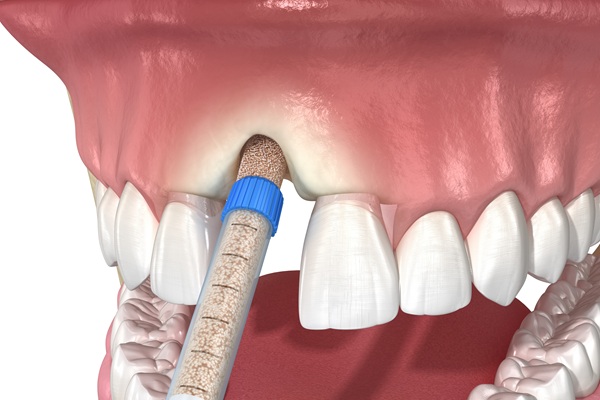

Bone grafting is a minor surgical treatment done under local anesthetic to replace depleted bone tissue. The grafting material may be inserted into a tooth socket just after a tooth is removed or at a location where a tooth has been absent for an extended period. Over the next few months, your body will produce new bone cells to replace the transplant material. Frequently asked questions about this procedure include the following.

It may originate from several places, including the patient’s body. That said, synthetic materials and laboratory-processed bone from a human or animal donor are now often utilized.

Grafting material derived from the patient’s body poses no health risk. However, this procedure has a drawback because it necessitates the creation of a second surgical site where the bone material is sourced. Mineral bone alternatives, whether made from human or animal bone, represent a low danger of infectious disease transmission because they are thoroughly tested before use. Therefore, graft materials have been demonstrated to be exceedingly safe. Also, mineral transplant materials do not stay in the body but are absorbed and replaced gradually by the natural bone.